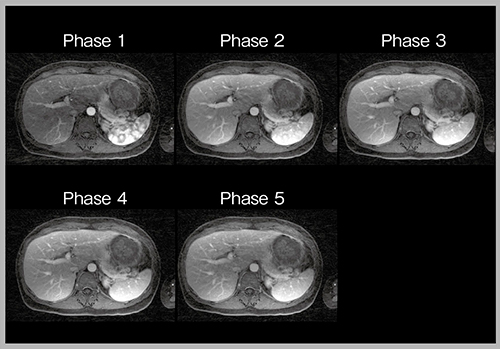

1)高速撮像(CS & PI)による多時相化

高速撮像法であるparallel imaging(PI)とcompressed sensing(CS)を組み合わせて動脈相に用いることで,従来の1相分の撮像時間(16秒)と同等の18秒で3相(1相6秒)の多時相撮像が可能となる。

図3は腎細胞がん(RCC)膵転移症例の動脈相の画像であるが,3相目(c)では描出されない微小な転移が,膵実質が濃染される前の1相目(早期動脈相:a)では確認できる。患者ごとに適切な動脈相のタイミングが異なるため,多時相撮像はきわめて有用である。

図3 高速撮像による動脈相の多時相化(RCC膵転移)(W.I.P.)